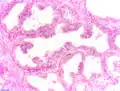

Histologie

Le diagnostic est obtenu par des biopsies prostatiques multiples, réalisées de manière échoguidée et par voie transrectale. Elle permet également de réaliser le score de Gleason, de grande valeur pronostique.

.jpg) Adénocarcinome prostatique

Adénocarcinome prostatique.jpg) Adénocarcinome prostatique

Adénocarcinome prostatique- Adénocarcinome ; tissus indifférenciés

- Invasion périneurale par un adénocarcinome prostatique. HE, x400

Score de Gleason

La structure tissulaire des cancers de la prostate varie des formes différenciées (cellules cancéreuses ressemblant aux cellules saines), dite de grade 1, aux formes les moins différenciées (cellules cancéreuses présentant beaucoup de caractères atypiques par rapport aux cellules saines), dite de grade 5.

Plusieurs grades peuvent se rencontrer au sein d'un même tissu. Le score de Gleason est calculé de la façon suivante : on additionne les deux grades les plus représentés de la tumeur. Le premier chiffre représentant le score du contingent le plus représenté. Ainsi 4+3 est plus péjoratif que 3+4

Si la somme est de 6 ou moins, le cancer est dit bien différencié, donc de meilleur pronostic ; 7 : le cancer est moyennement différencié ; 8 ou plus : le cancer est peu différencié, donc de moins bon pronostic.